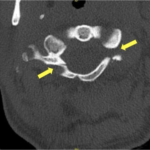

The Jefferson fracture classification system describes fractures of the atlas (first cervical vertebra or C1). Jefferson fractures with potential tears in the transverse ligament can cause cervical spine instability and can result in neurologic injury if not appropriately diagnosed and managed. We present the case of a 54-year-old man who fell head first with cervical spine tenderness and upper extremity paresthesias. The patient’s Jefferson fracture was diagnosed via computed tomography. The patient was then treated non-operatively for his Jefferson fracture, and he had an unremarkable hospitalization. Emergency physicians should obtain surgical consultation and consider the possibility of ligamentous injury in patients suffering injury to the cervical spine.